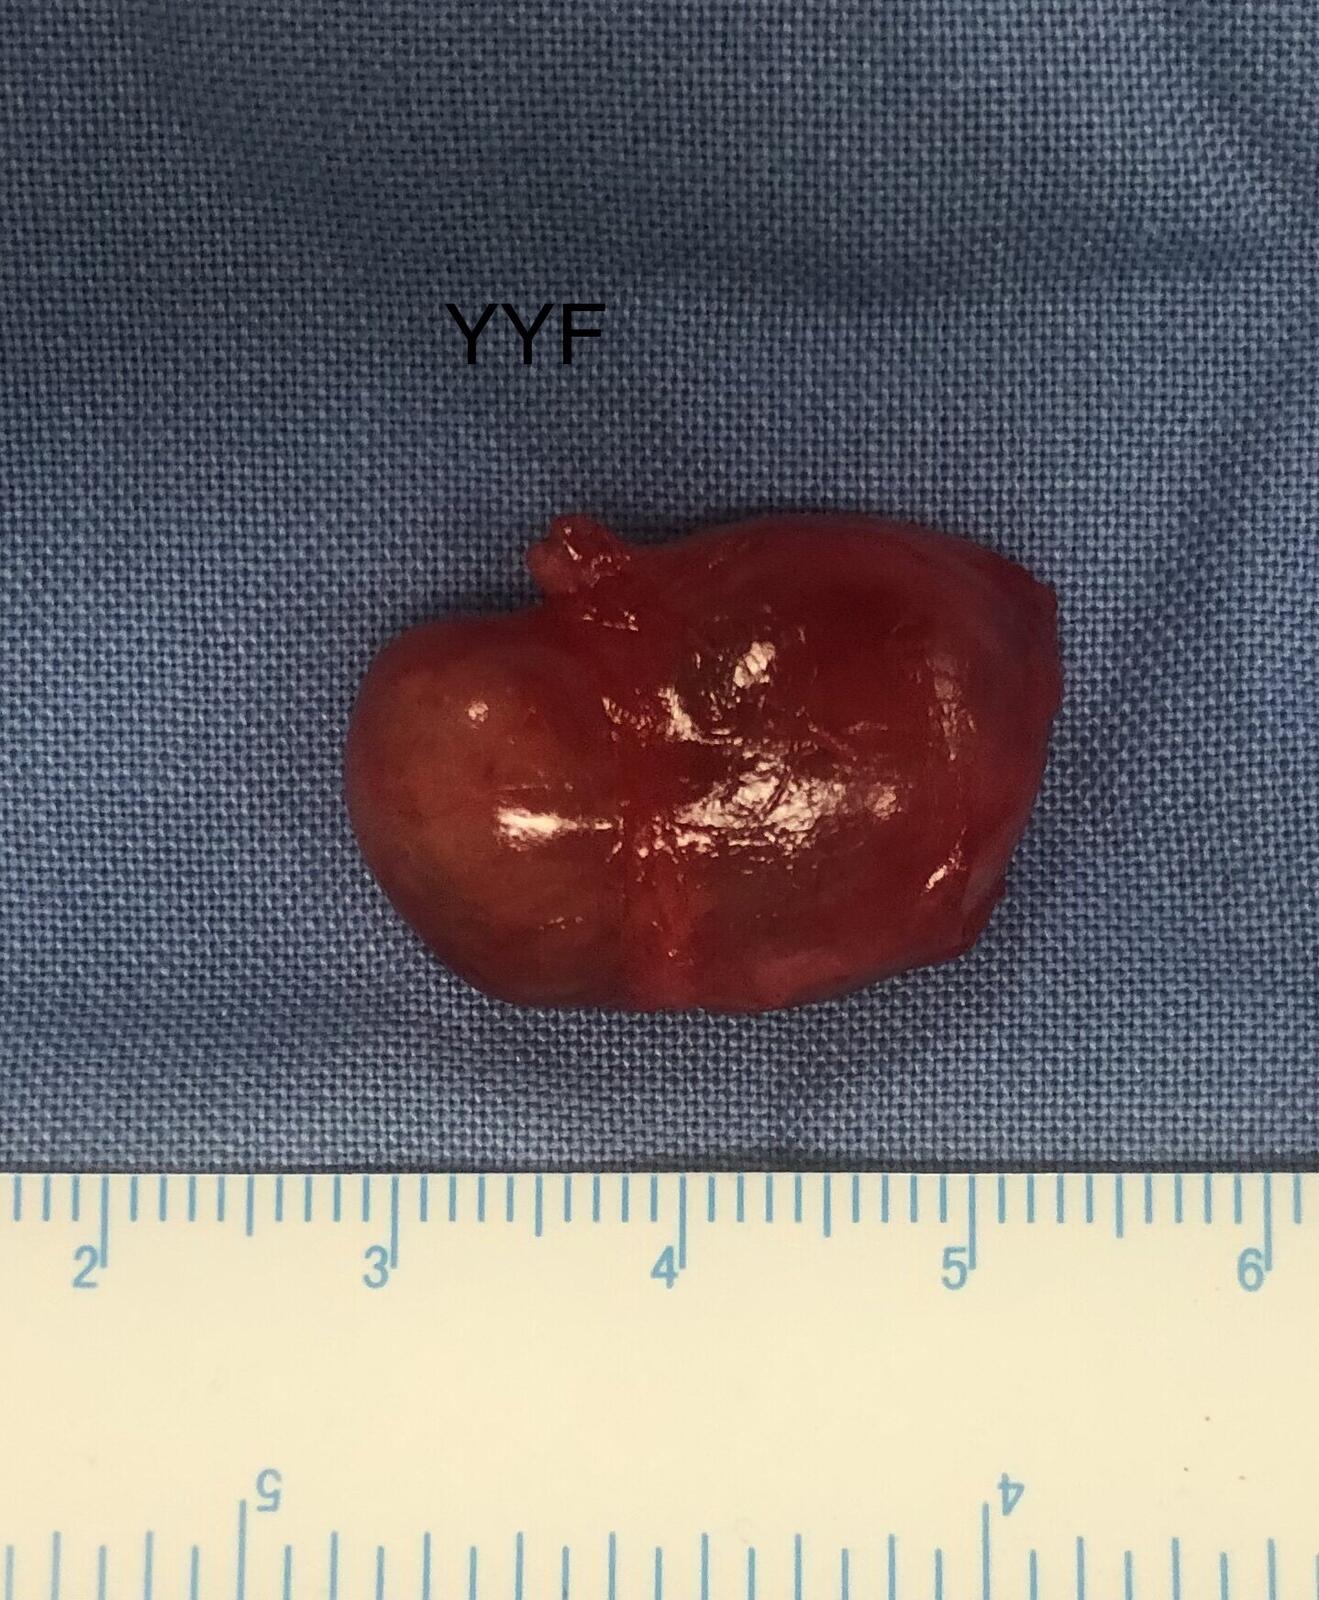

完整摘除是避免复发的唯一要素。

白色区域为病变起源的神经纤维

最终病理为神经纤维瘤,

其发病率远低于同为神经起源的神经鞘瘤。